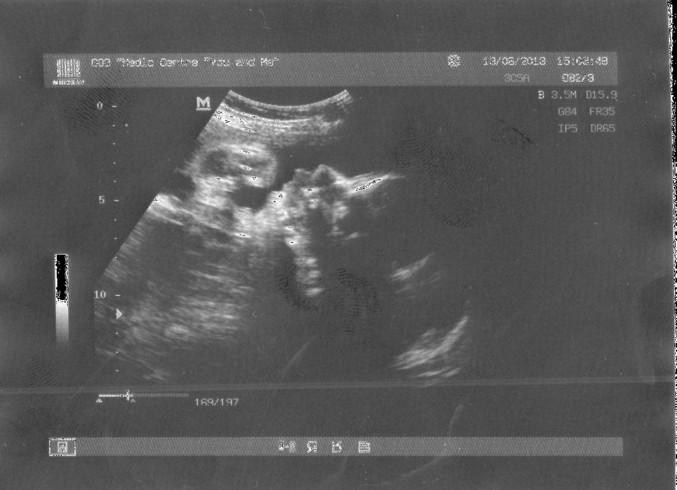

Ну так вот-узи было обычное не 3D, а разница большая-лично мне очень понравилось оно))))Всё с малышом хорошо-развиваемся без пороков, ну и под конец мне выдали-знаете единственное у вас у малыша обвитие пуповиной у шеи.......вот так да....и такая сидит-а так кровоток хороший-всё хорошо.....мдааассьь знаю что это обвитие ничего страшного что и с 2-ным рожают...но я не думала что у нас такое-что нас коснётся. Вот во вторник пойду в церковь попрошу боженьку чтоб он помог малышу распутаться(время ещё есть) и иконку в кроватку куплю....

Вот подскажите мне что-то я вес малыша не могу понять каков он?не 1 кг и 800 грамм случайно, просто так написано, я вот и не пойму)))))и наш отчёт)))я и пирожочек(фото долго не могли сделать, рукой закрывался))))))))

Вот может кто из вас подскажет вес малыша?)))))Кстати и подтвердили что у нас МАЛЬЧИК ПИРОЖОЧЕК)))))))

Наш сладенький пирожочек)))